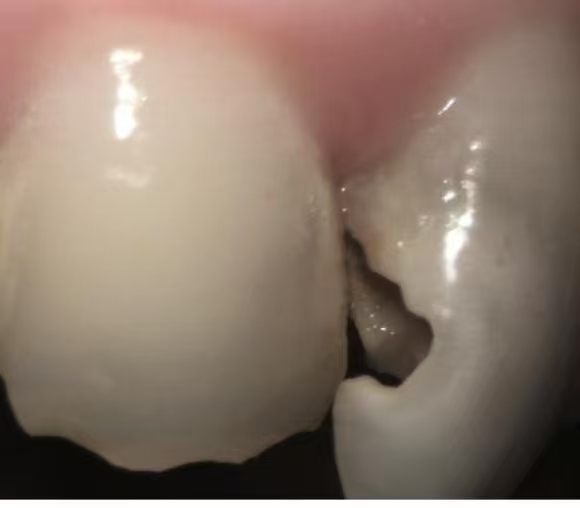

Oral health plays a vital role in daily life. Healthy teeth allow individuals to eat, speak, and smile confidently. However, neglecting dental care can lead to severe consequences. For example, tooth decay is a common problem that affects many people. It can occur even with good hygiene practices due to factors like genetics and diet. In fact, many people experience dental issues despite their best efforts. A personal story illustrates this point: a front tooth began to decay, gradually worsening over the years. Although the initial damage seemed minor, it eventually required extensive treatment. This emphasizes the importance of addressing dental problems early to prevent further complications.

Through the consultation, a root canal procedure was recommended. Surprisingly, the cost was reasonable compared to other options. Temporary fillings provided relief while waiting for a more permanent solution. After nearly a year (not recommended though this was not per doctor’s instruction. ), a follow-up appointment resulted in a thorough filling that restored the tooth’s function and appearance. The dedication of the dental professionals made a significant impact on the overall experience, illustrating the value of choosing the right dental care provider.